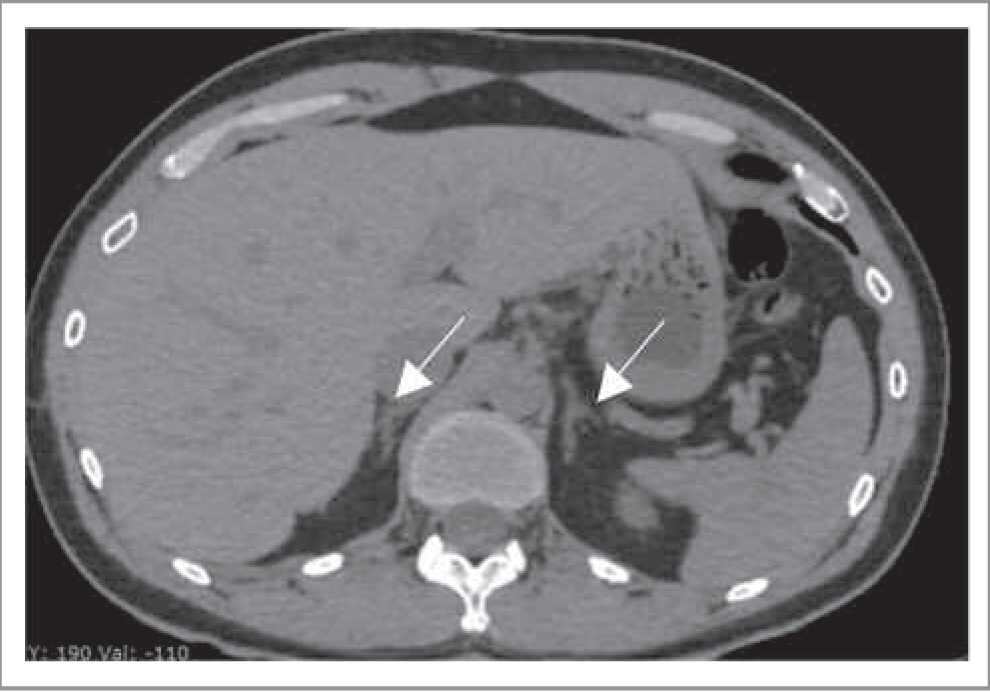

КТ-критерии метастатического поражения часто сходны с таковыми при АКР. Для метастазов характеры: нечетко очерченные контуры, высокая плотность образования (более 15 ед. Н), неоднородность структуры, а также слабое вымывание контрастного препарата при болюсном контрастном усилении. Однако небольшие по размеру метастазы могут быть однородными, в то время как атипичные аденомы, наоборот, могут быть неоднородными. Гиперконтрастные метастазы (например, рака почки) следует дифференцировать с феохромоцитомой (рис. 9). Двустороннее поражение надпочечников более характерно для метастазов, чем для аденом (50% против 10–20%) [11]. Кроме того, в отличие от аденом, метастазы значительно быстрее растут при динамическом КТ-контроле через 6 мес.

Рис. 9. Метастазы светлоклеточного рака почки в надпочечники. МСКТ, аксиальная проекция, АФ. Гиперденсные округлые солидные образования в телах обоих надпочечников.